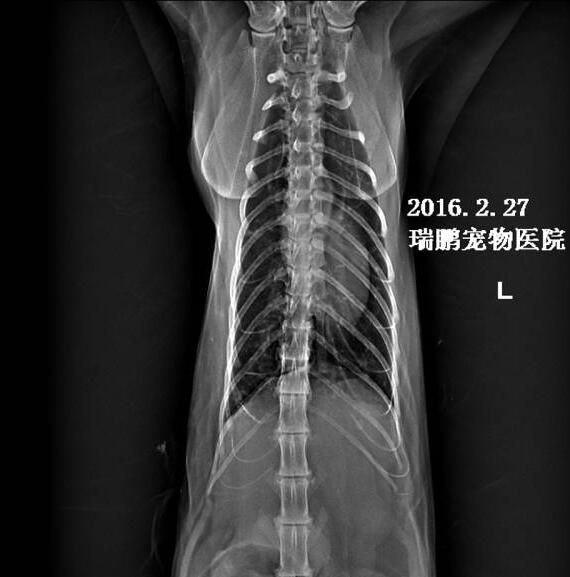

3.4 X线检查:肺部未见明显异常(见图1、2)。

图1 胸部X光侧位片

图2 胸部X光正位片